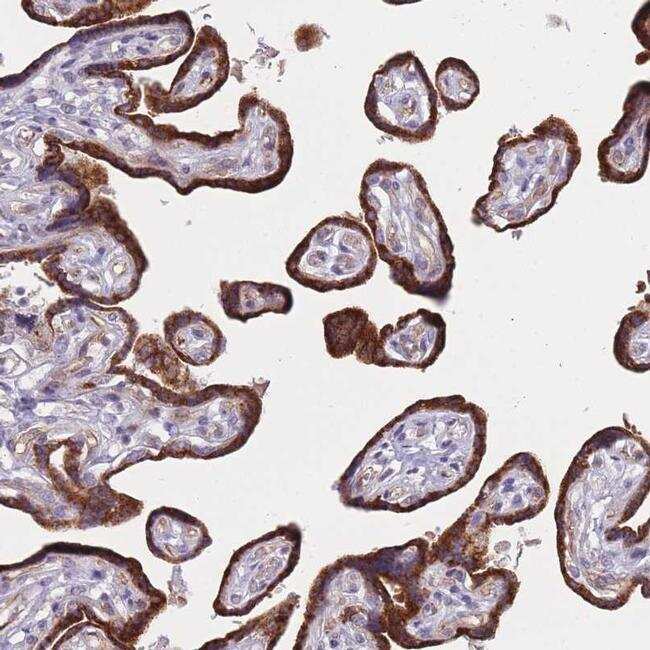

- Immunohistochemical analysis of FAM227B in human placenta using FAM227B Polyclonal Antibody (Product # PA5-62039) shows strong cytoplasmic positivity in trophoblastic cells.